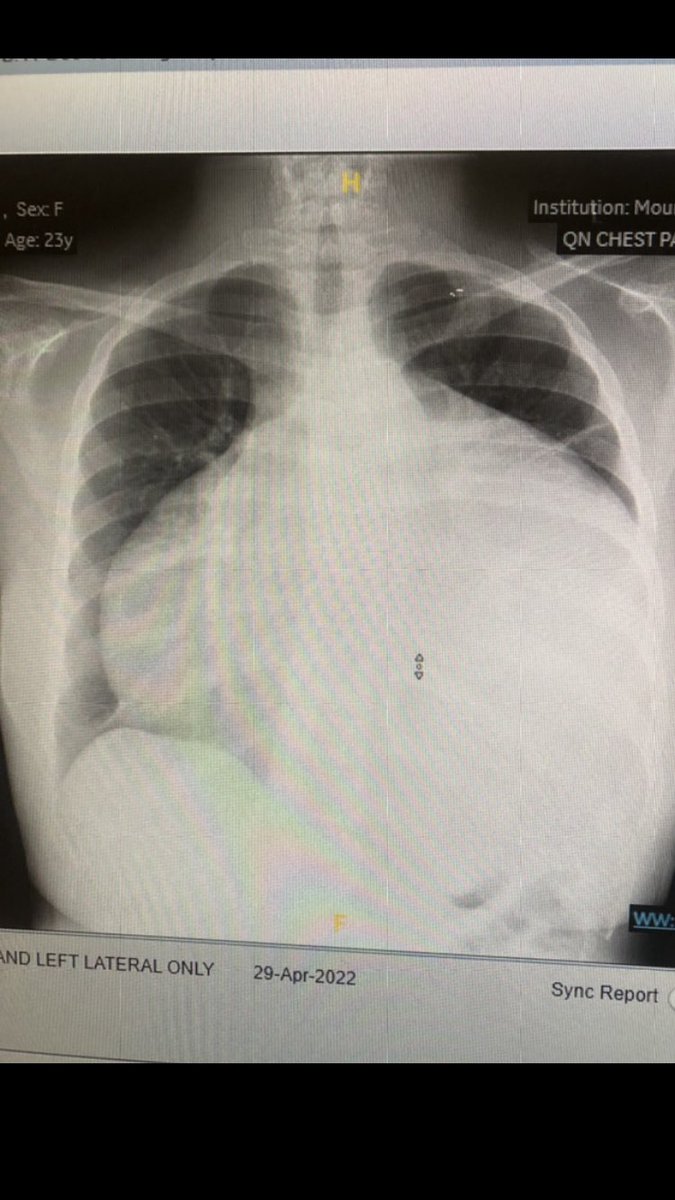

Happening now in the Mount Sinai CV Reading Room.

What's your diagnosis ?